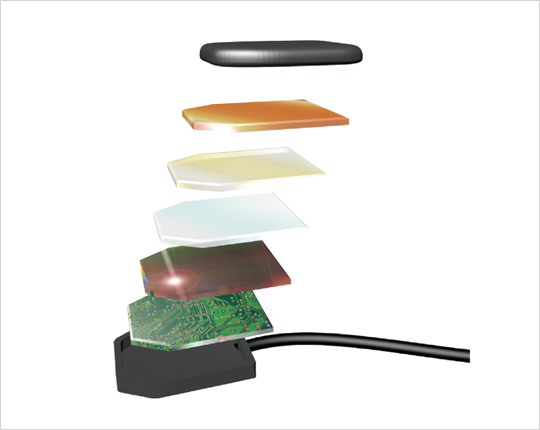

¿Cómo creamos un sensor de tan alta calidad?

- Nuevo algoritmo de procesamiento de imágenes aplicado

- Factores de imagen bien equilibrados: resolución, sensibilidad y ruido

- Componentes de fabricación interna (desde el diseño de CMOS hasta el software de visualización)